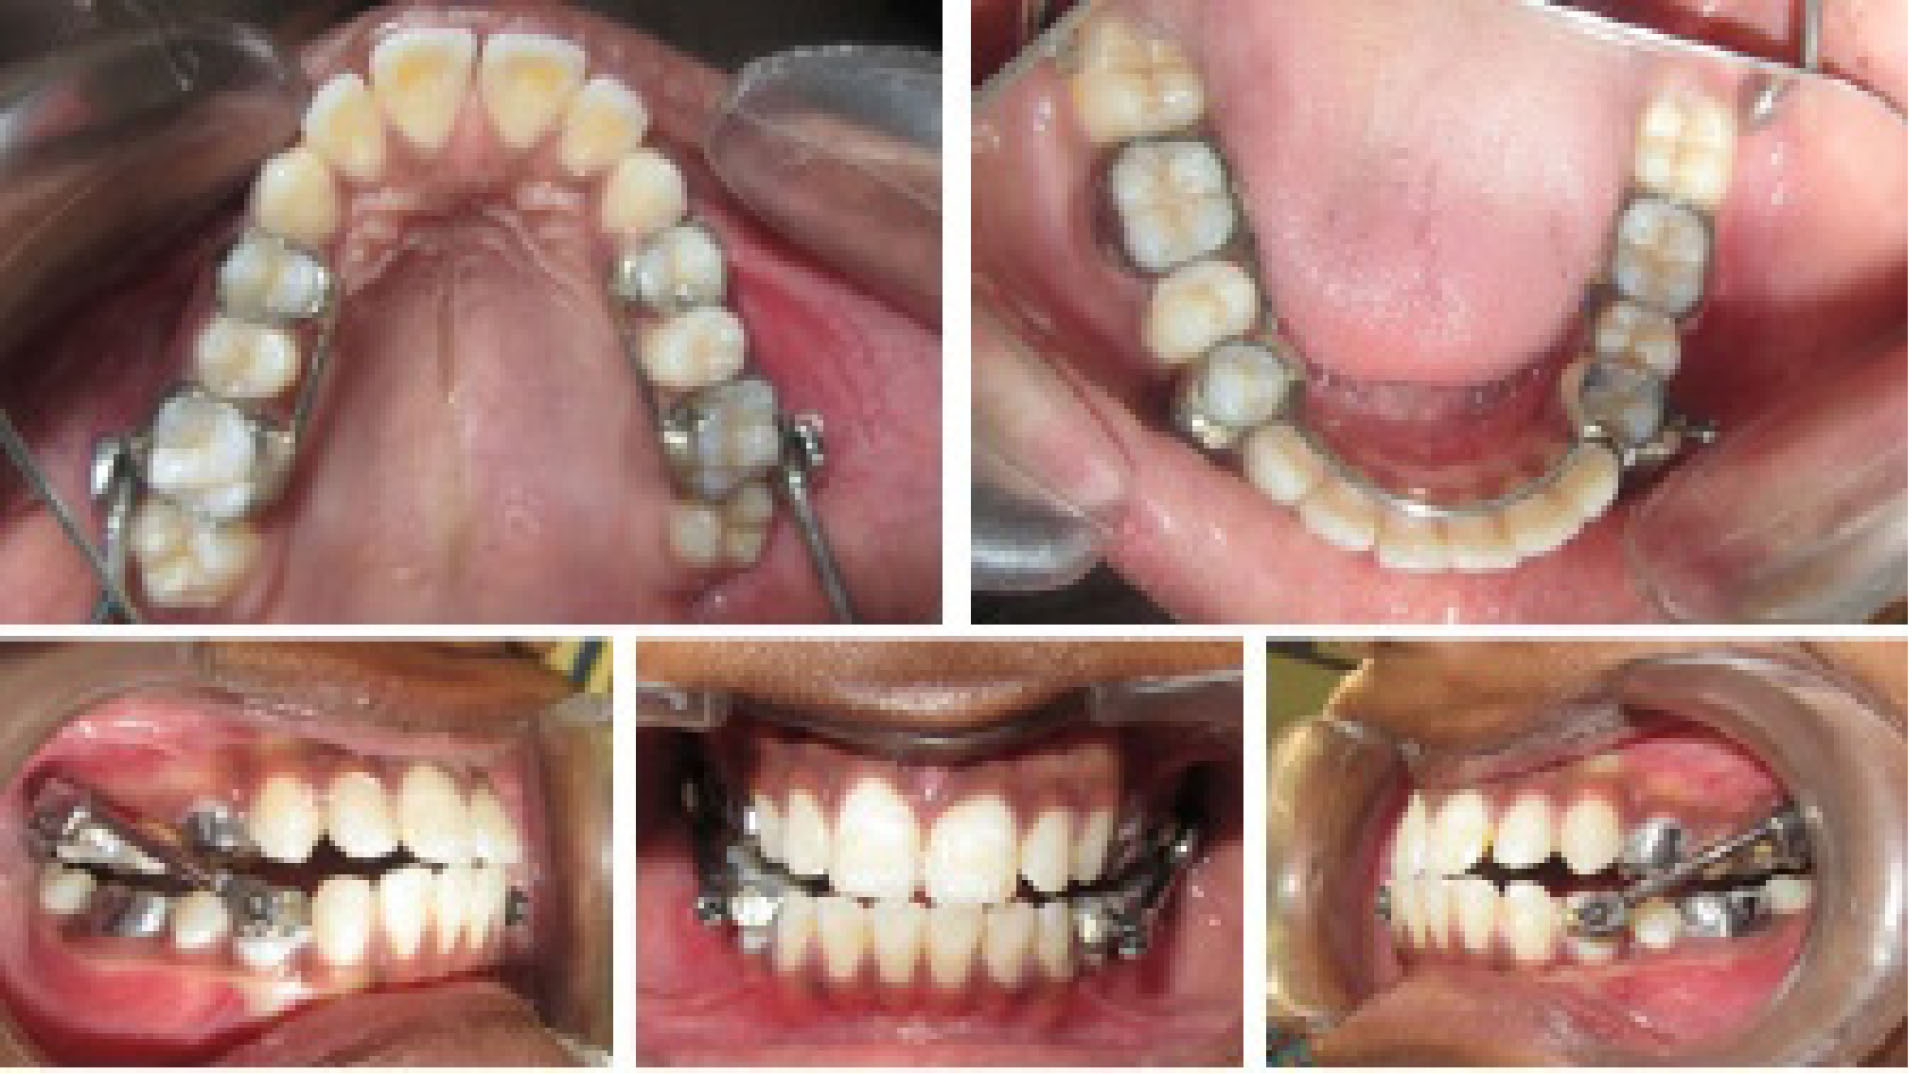

Standardized lateral cephalometric radiographs ().

Intraoral photographs ( and ).

Standardized lateral cephalometric radiographs at T1 and T2.

Intraoral photographs at T1, depicting partial anchorage in the upper arch and total anchorage in the lower arch.

Intraoral photographs at T2, depicting the end of functional phase.

(). Upper first molars and first premolars were banded, and the anchorage was reinforced with a 0.032” stainless steel lingual wire soldered to the first molar and first premolar on each side ().

The anchorage design for the appliance consisted of total anchorage in the lower arch by the inclusion of teeth from the first molar on one side to the contralateral side in the lower arch, with partial anchorage in the upper arch by the inclusion of the first premolar to the first molar on each side (). Achievement of class I molar relationship marked the end of the functional phase, and a change in the molar relationship was assessed easily by removing the tubes and plunger. Since it works by snap fit over the ball joints, removal and insertion are quite easy.